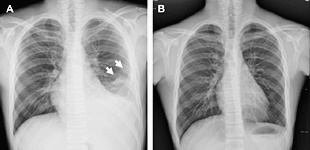

흉부X선 검사와 늑막 생검으로 진단이 가능해요. 청진시 호흡음이 감소되거나 가슴을 두드렸을 때 둔탁한 느낌이 들기도 합니다. 진단에 명확하지 않은 경우 흉강내시경을 이용하기도 해요.